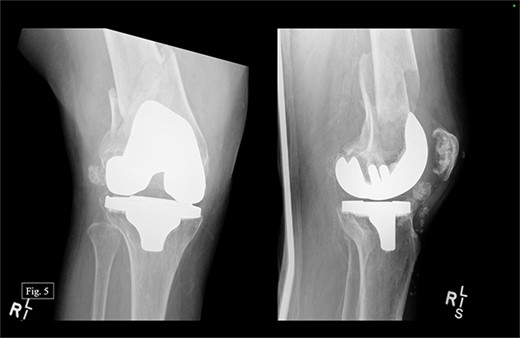

The patient presented to our level 1 trauma center in September 2022 with acute right knee pain and unable to ambulate. She was seen and evaluated in the emergency department, where she was found to have evidence of a right distal periprosthetic femur fracture (Su Type II) after a ground-level fall (Fig. 5). Because of the open box configuration of the native TKA implant and adequate available bone stock, a standard Stryker right retrograde intramedullary nail (IMN) was selected.

The patient was positioned supine with a radiolucent triangle under the operative knee. A trans-patellar approach was made for our T2 alpha retrograde nail measuring 10 × 330 mm. We confirmed the appropriate purchase with fluoroscopy and placed the distal interlocking screws through the implant. The distal articular block was noted to be slightly valgus; however, it appeared appropriate when assessing her mechanical and clinical alignment. The patient experienced 100 mL of intraoperative blood loss, awoke without incident, and was admitted to the ICU for monitoring and management. Postoperative APand lateral X-rays were taken (Fig. 6).